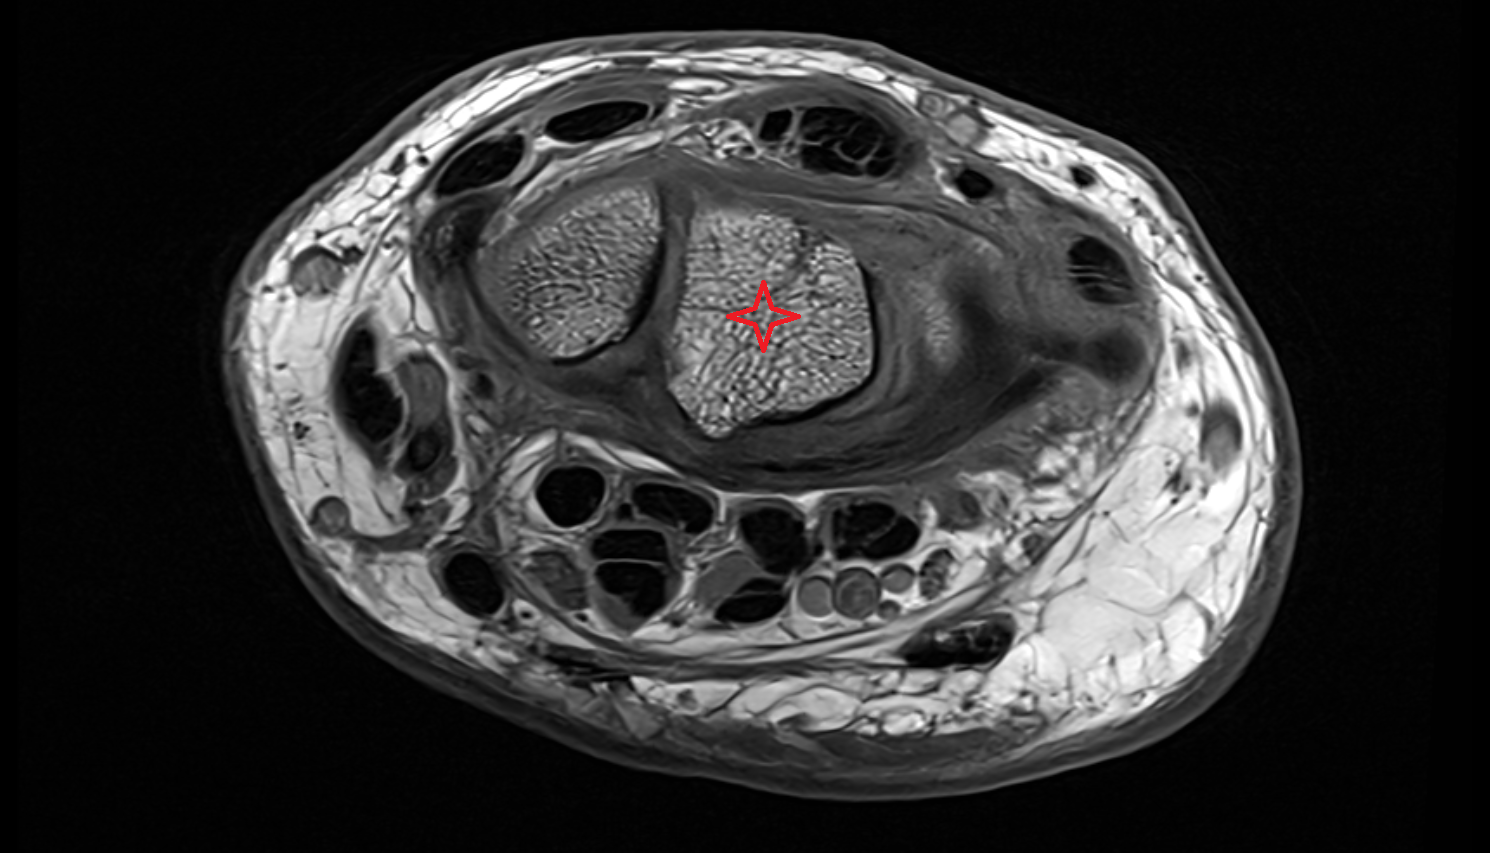

- Fetal elbow